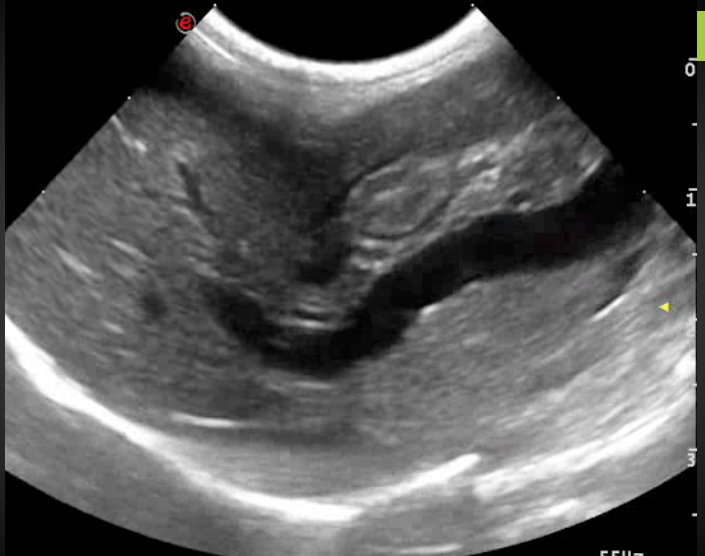

• Expliquer les principes de formation de l’image échographique et identifier les paramètres techniques nécessaires à l’obtention d’une image de qualité : choix et réglages de l’appareil, préparation de l’animal, protocole de réalisation de l’examen, etc.

– Identifier son aspect échographique normal

Pour chaque organe, un rappel illustré est proposé, couvrant l’anatomie topographique, la technique d’exploration échographique, et l’aspect échographique normal.

Le formateur réalise une démonstration en direct sur animal, illustrant la méthodologie d’exploration et l’identification de l’aspect normal de l’organe.

• Les rappels anatomiques et la présentation des images normales sont présentés par projection multimédia